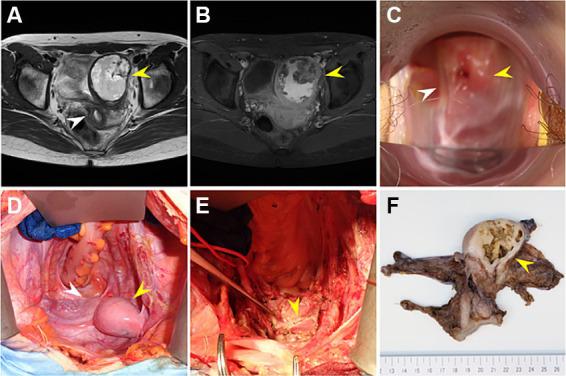

核受体亚家族5 A组成员1()基因编码NR5A1,也称为类固醇生成因子1,是一种调节肾上腺和性腺发育及功能的关键转录因子。虽然已知该基因的致病变异会导致一系列性发育障碍(DSD),但具有46,XY DSD且内外生殖器完全为女性的个体相对罕见。在此,我们报告一例46,XY完全性性腺发育不全(CGD)患者,该患者因该基因c.132_134del(p.Asn44del)杂合框内缺失而有一个不通的残角子宫,该缺失是在治疗一个不能忽视妇科恶性肿瘤的盆腔肿块时被诊断出来的。与之前两例携带p.Asn44del变异的病例不同,该病例表现为CGD,这是一种严重的DSD表型,并且我们发现诸如、、和等DSD致病基因的寡基因遗传可能影响了临床表型的严重程度。